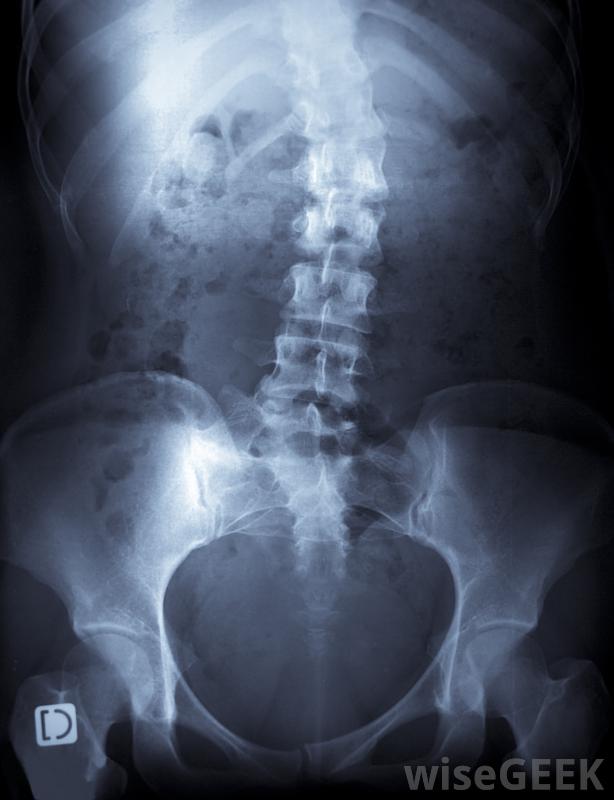

脊柱侧凸的物理治疗可采用推拿和手法操作特发性脊柱侧凸,也就是说没有已知的弯曲原因。脊柱在童年或青春期早期开始向一侧或另一侧弯曲,脊柱侧弯会变得非常严重。脊柱侧凸的治疗通常集中在阻止曲度的发展上。治疗方案的使用取决于具体病例的具体情况。一般来说,干预越快,患者可能的结局越好,这也是为什么建议对幼儿进行脊柱侧凸检查的原因之一,以便尽早发现脊柱弯曲。

脊柱侧凸会导致脊柱弯曲在脊柱侧弯理疗的情况下,患者定期与理疗师合作,并在家中进行锻炼,有时在家人的协助下进行。重要的是要看有脊柱侧凸理疗经验的理疗师,人们通常会与临床医生和物理治疗师同时工作,以确保治疗过程保持适当和有效。